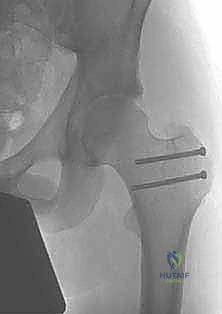

تُخاط الكبسولة بإحكام، ثم يُعاد عظم المدور الكبير إلى مكانه الأصلي ويُثبت باستخدام براغي طبية (Screws) مصنوعة من التيتانيوم لتأمين التئام العظم.